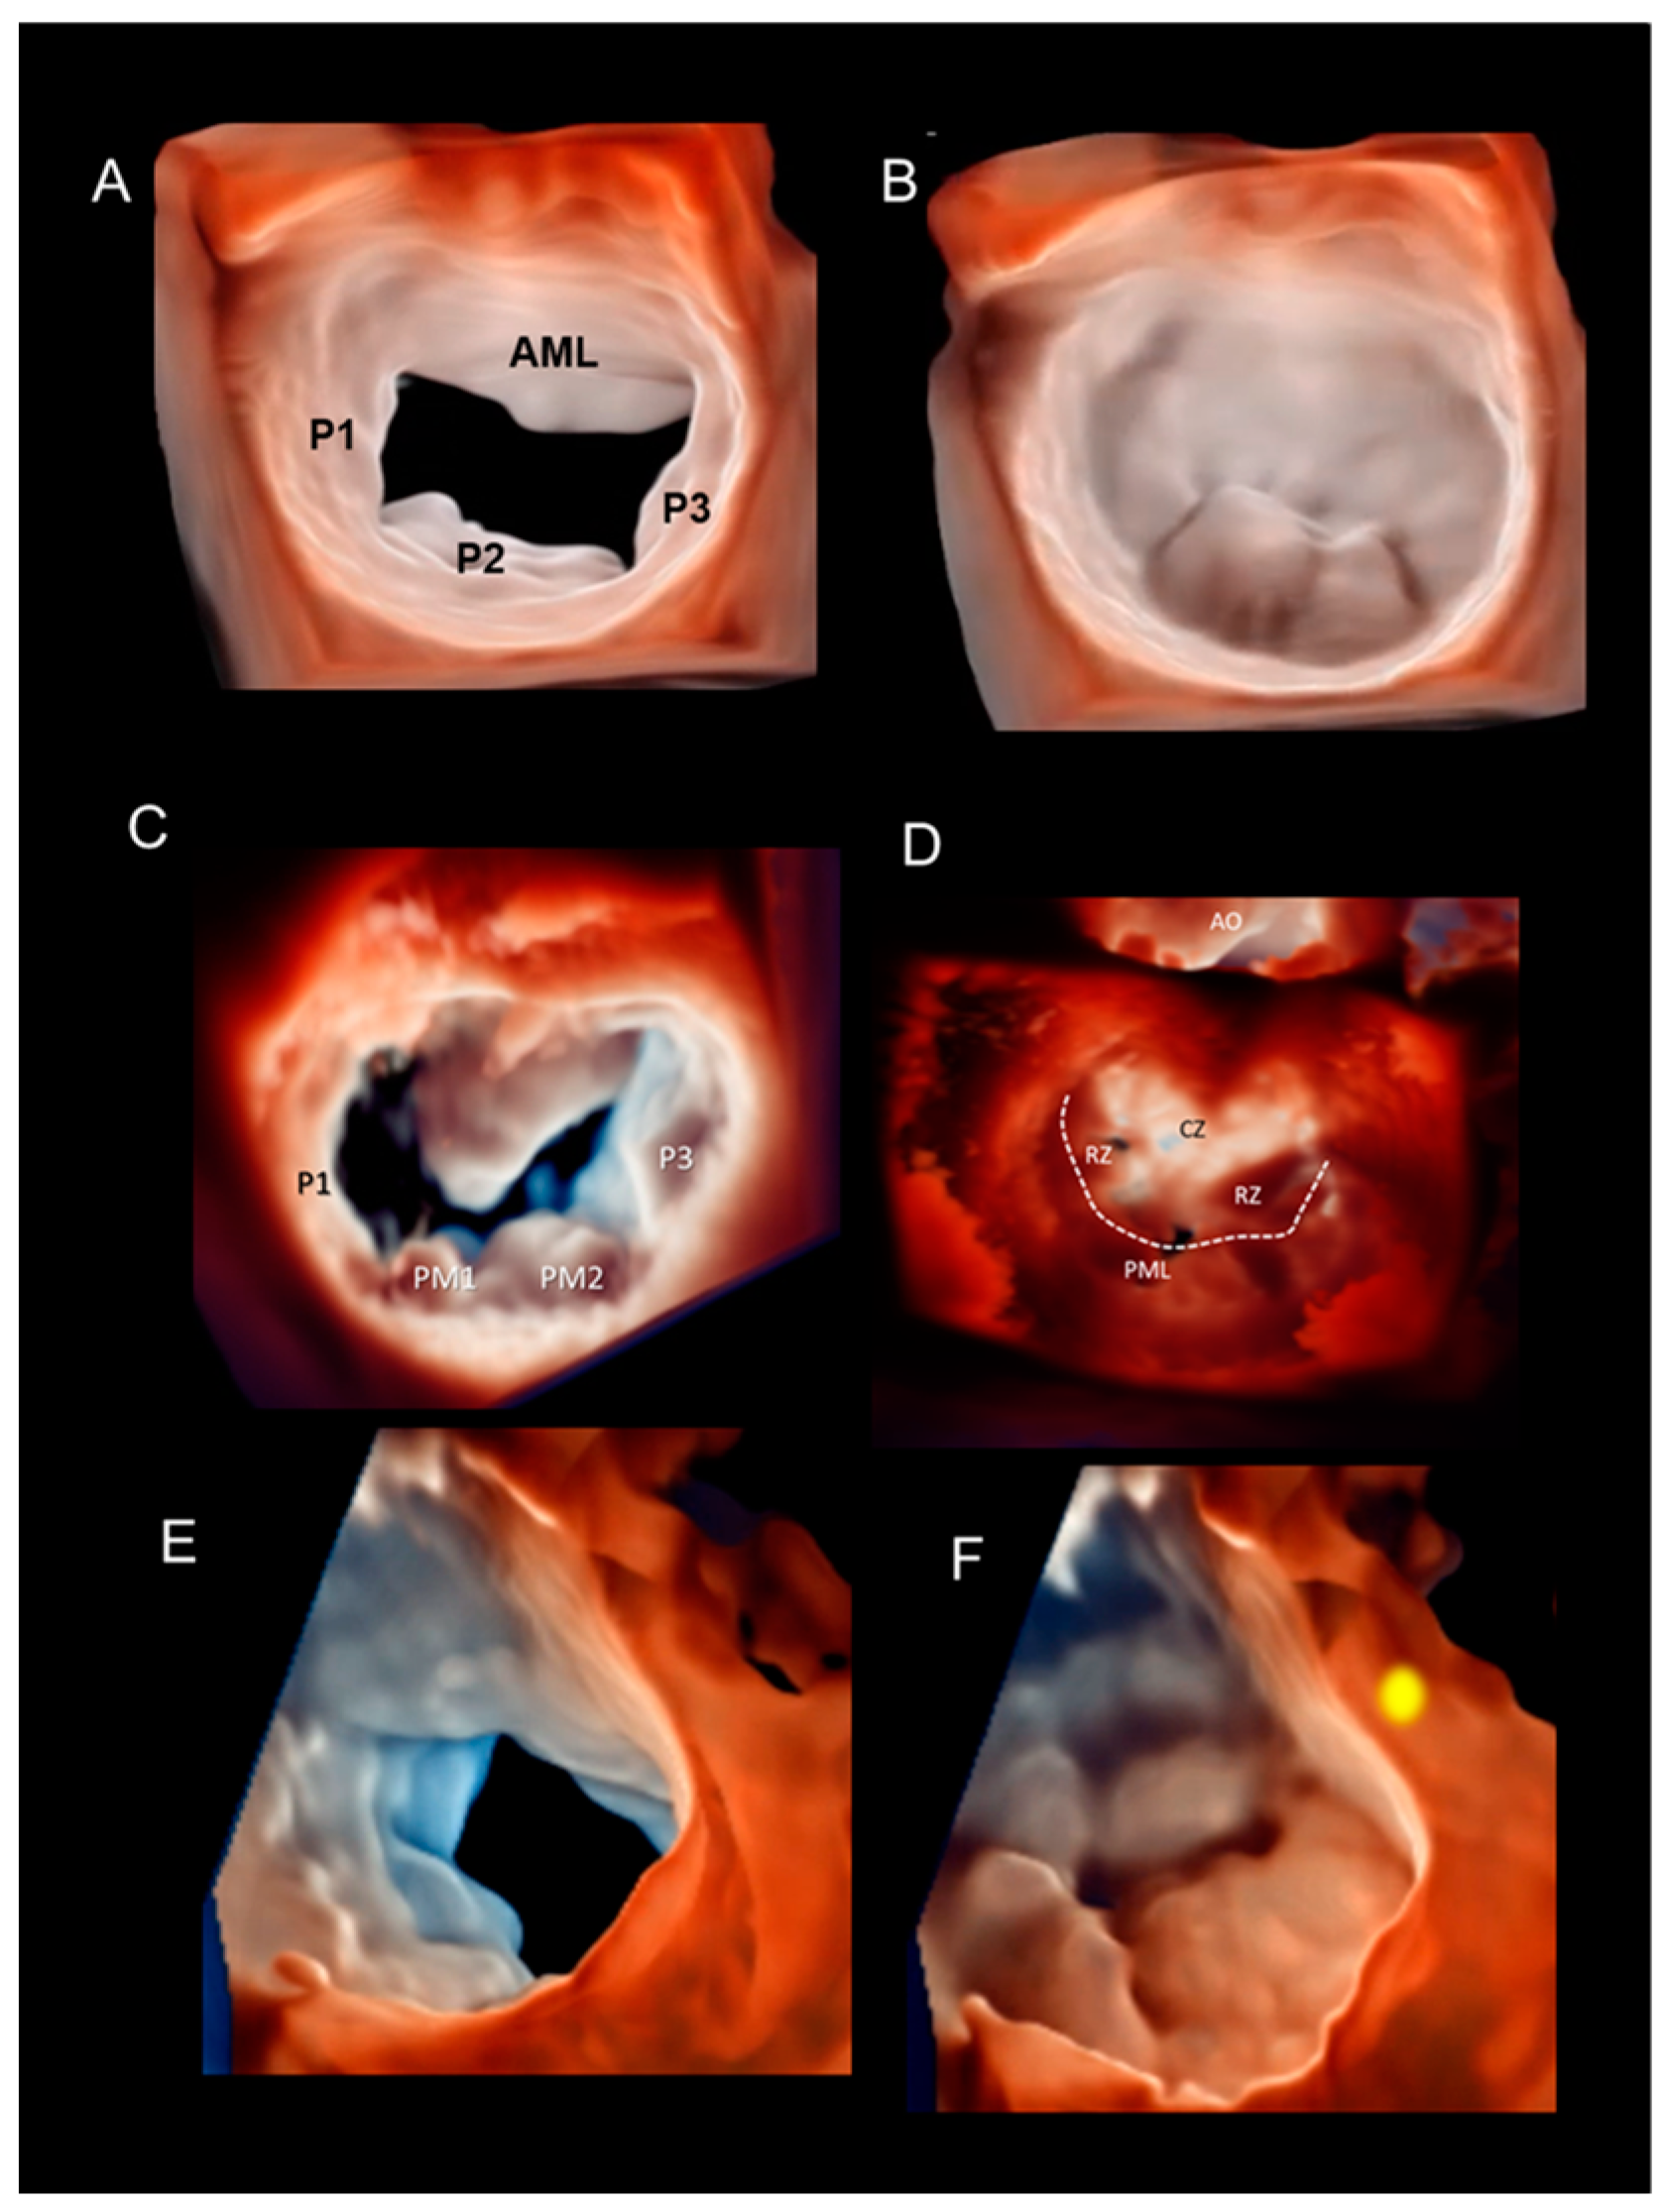

Multiple Perspectives

Phenotypes of DMVR